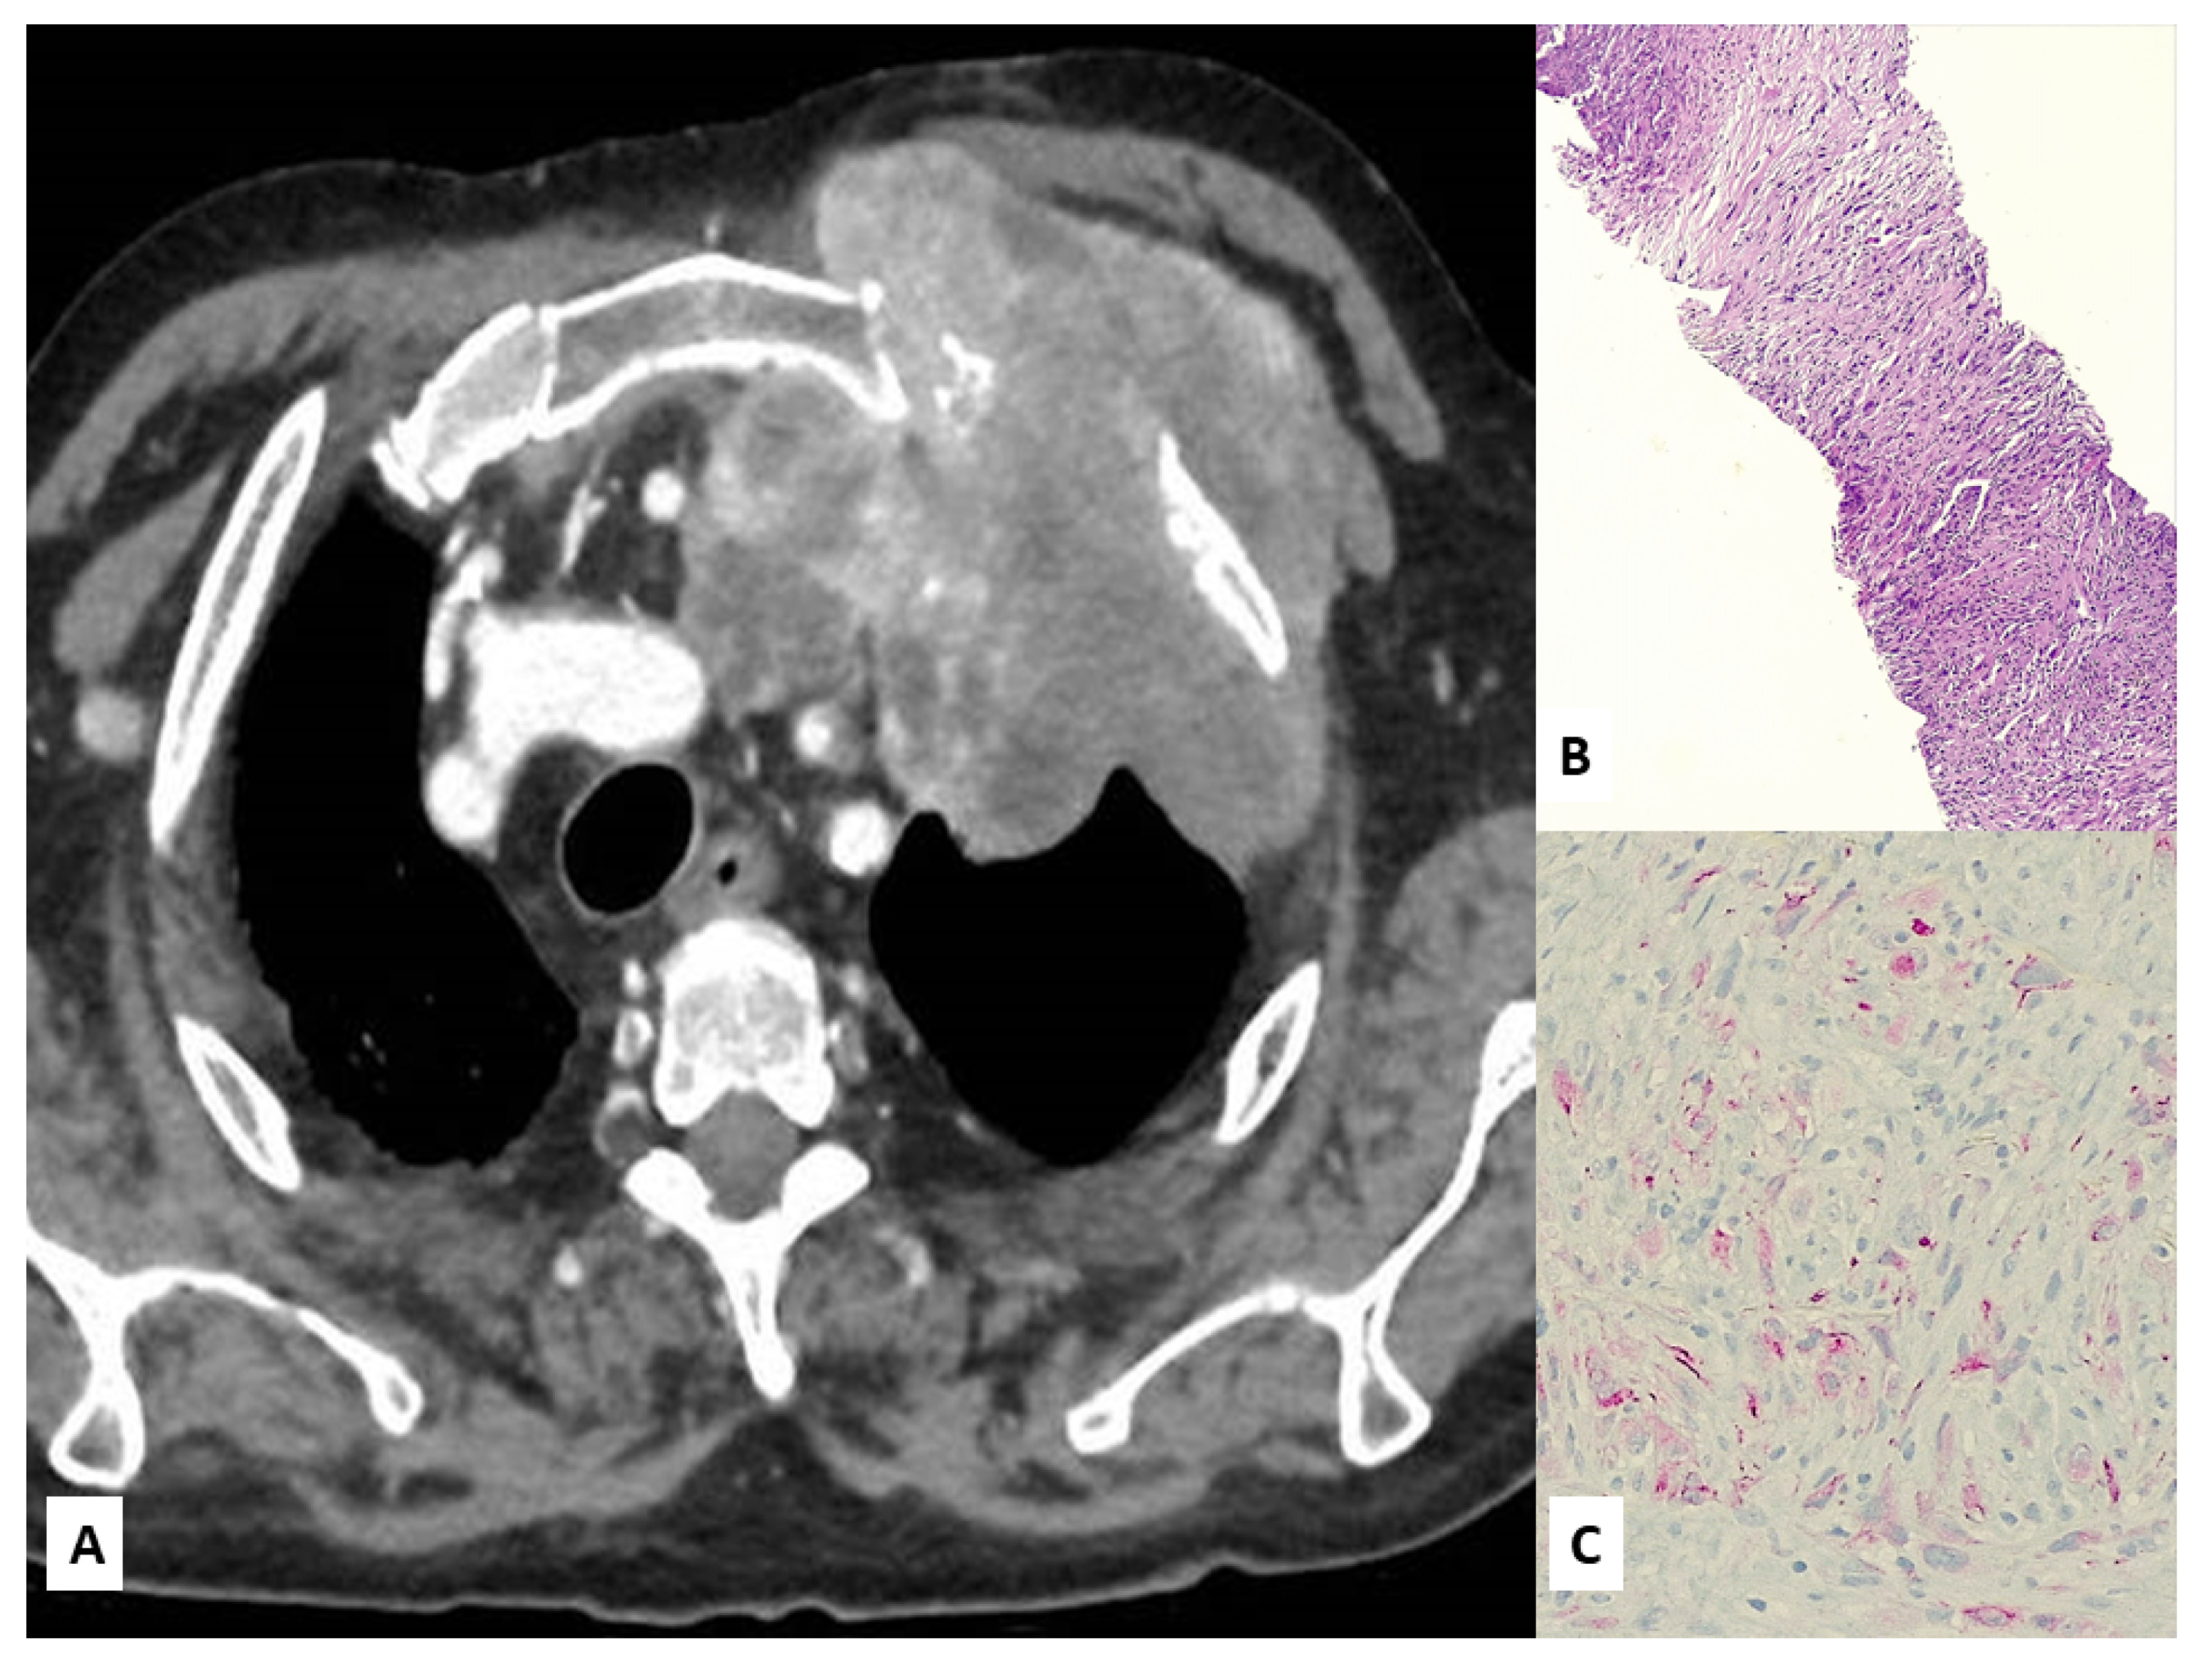

3. Unusual Radiological Presentation

4. Unusual Morphologic and Immunohistochemical Features